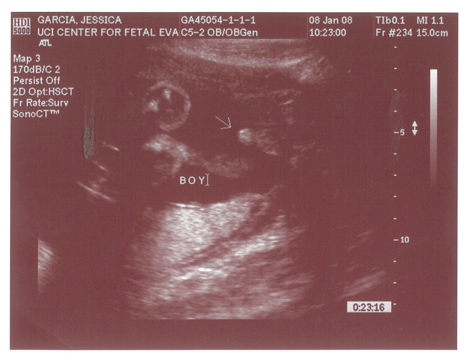

Babies First Pictures!!! ITS A BOY!

Yes we got a new dsmer coming into the world soon. We got our ultrasound today and its gonna be a boy. And shes a lot further along then we had originally thought. Shes due on April 15th which puts her at almost 6.5 months, (and really not showing it.) He weighs currently ~2lbs. He even opened his mouth while on camera which was really cool.

Here are the pics.

Pic 1: The babies head profile

Pic 3: NWS Baby Penis! lol